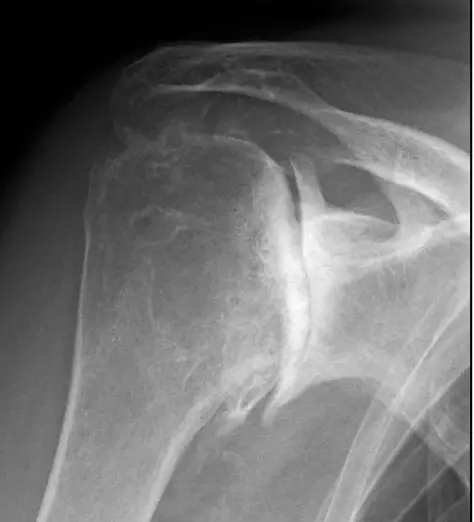

Röntgen filmi çoğu zaman omuzdaki hasarı belirlemek için yeterlidir. Kemikler arasındaki normal eklem boşluğunun kaybı, kemiğin şeklinde düzleşme veya düzensizlik, kemik mahmuzları ve eklem içinde yüzen gevşek kıkırdak veya kemik parçaları röntgen ile tespit edilebilir.

Artroz gelişmiş omzun ön-arka grafisi